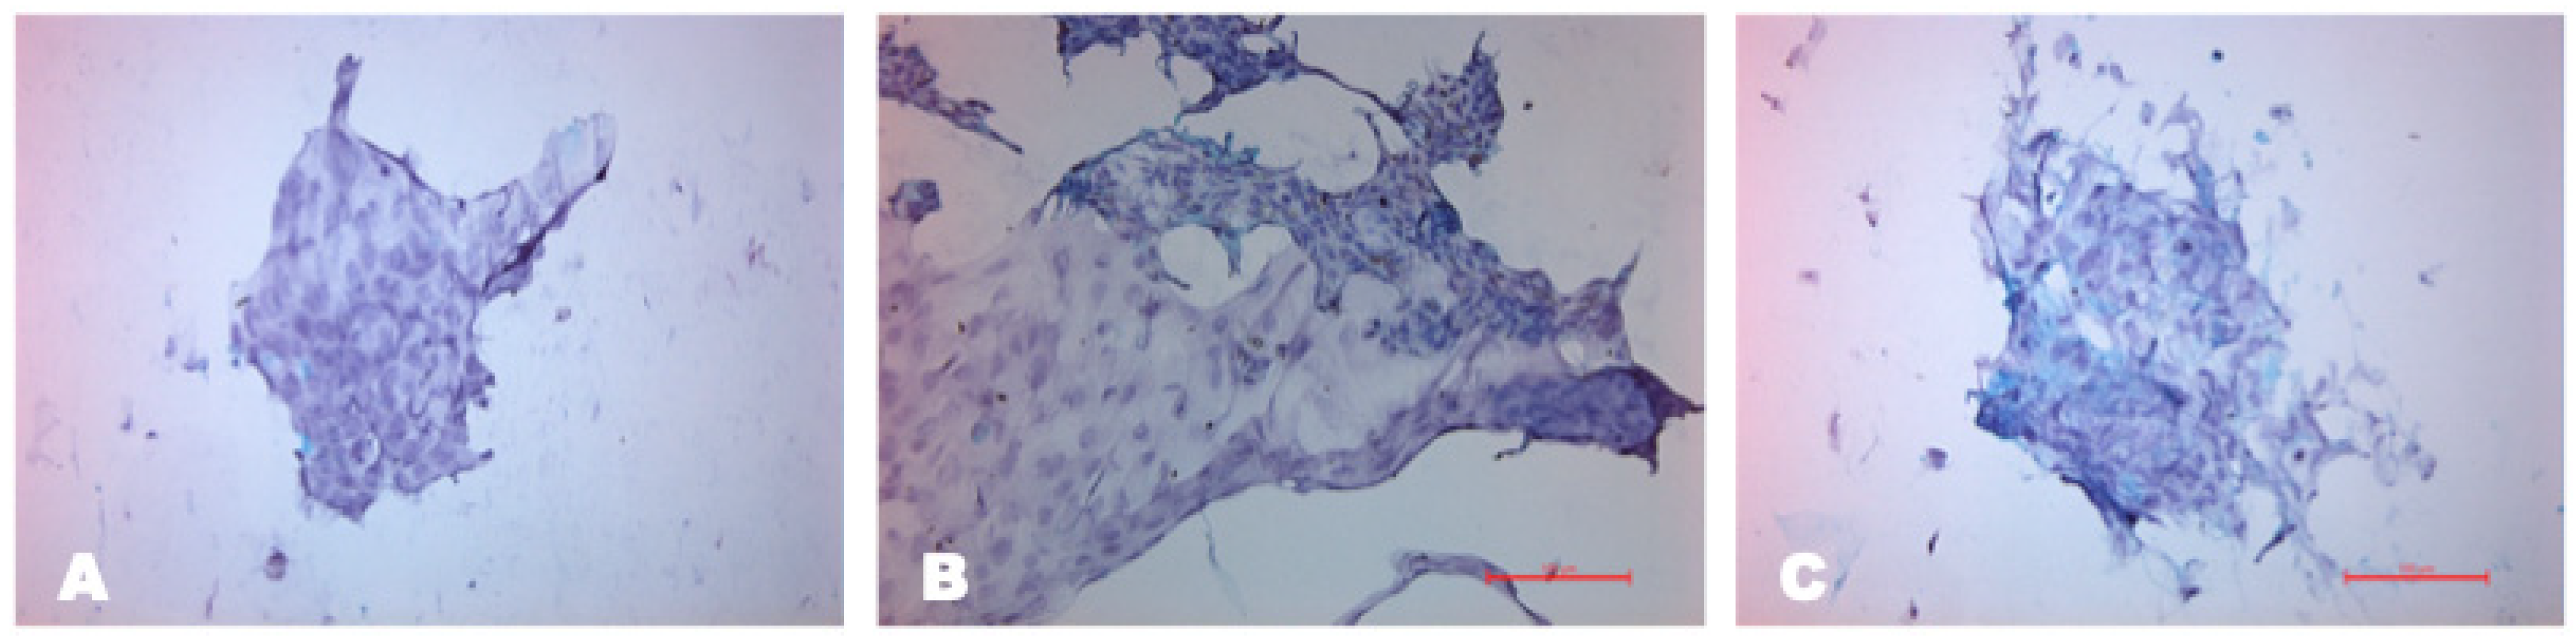

Impression Cytology

According to the results of impression cytology, 30 days after LSCD modeling, the conjunctivalization of the central and peripheral parts of the corneal epithelium was revealed. The presence of goblet cells was noted in these zones, which were absent in the healthy eye. This is the most reliable diagnostic criterion for the diagnosis of LSCD, which indicates a successful animal model (Figure 8).

Figure 8. Impression cytology in different anatomical areas of the eye after LSCD modeling with PAS staining, scale bar: 100 μm. (A) Conjunctival epithelial cells with high nuclear/cytoplasmic ratio; (B) in the limbal area, borderline between conjunctival and corneal epithelium; (C) blue periodic acid–Schiff-positive goblet cells stained with mucin were observed in the central cornea.

Biomedicines 12 00101 g008